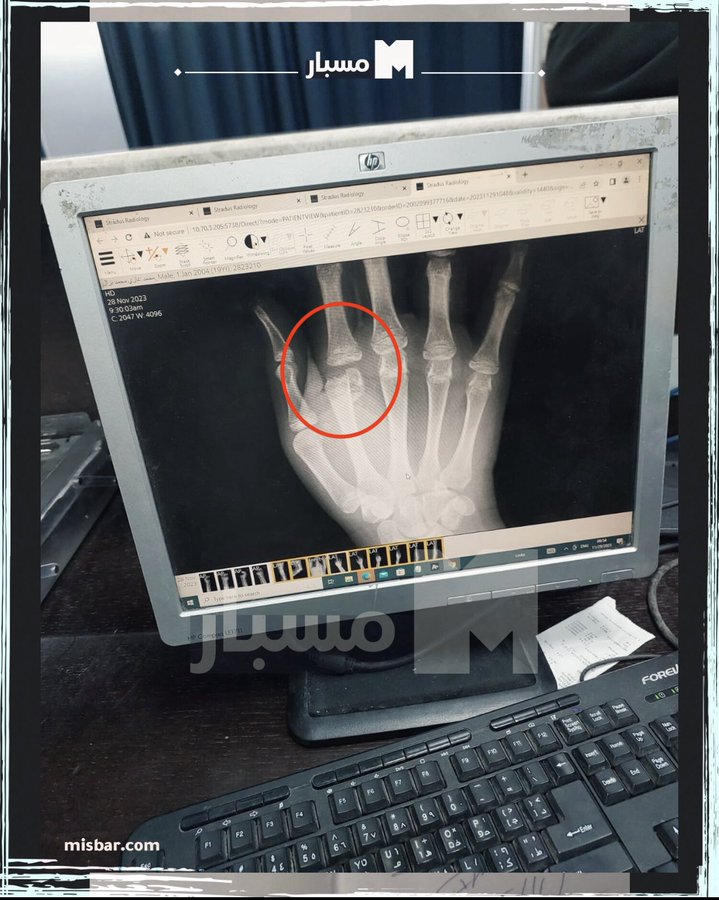

BREAKING: MEDICAL RECORDS OF MOHAMMAD NAZAL SHOW HE WAS TELLING TRUTH ABOUT BROKEN ARMS, FINGERS AND BEING BEAT

The report shows he had fractures in his fingers, contusions in his right and left arms

His report states;

“X-ray showed RT 2nd Metacarpal Head Displaced Fracture & Left 2nd Metacaroipal Shaft Minimally displaced fracture trial of reduction and bilateral below elbow splint in positive hand plus position applied"